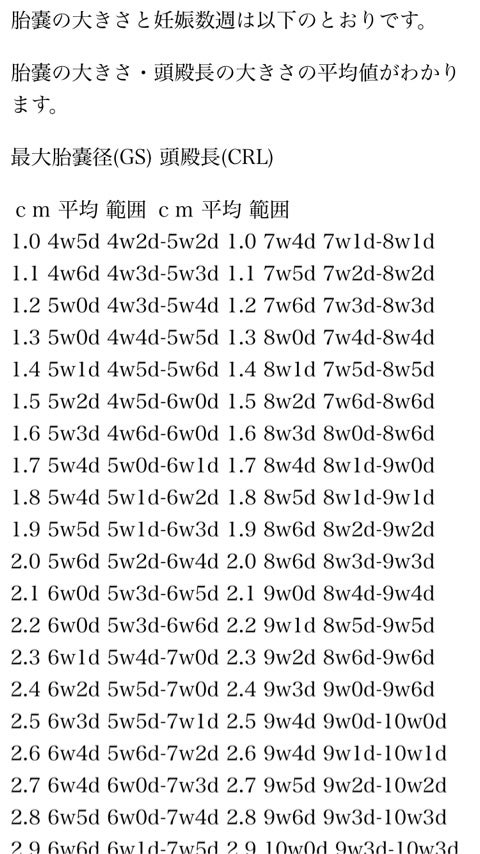

胎嚢の大きさの平均サイズ グラフ 妊娠データ